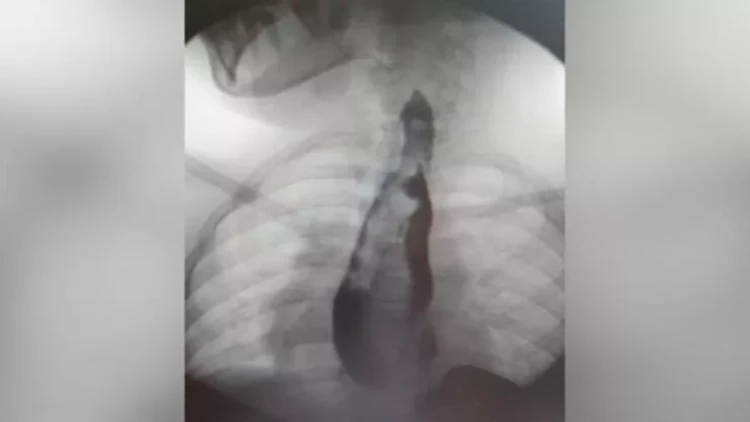

meqale.com lente istinadən bildirir ki, 14 yaşlı məktəbli qız qarın nahiyəsində vaxtaşırı ağrılardan şikayətləndiyi üçün ailə yaşadıqları yer üzrə klinikaya müraciət edib. Müayinə zamanı nadir bir patoloji - yemək borusu və mədənin qoşa olması aşkarlanıb.

Hər iki cüt orqan, demək olar ki, bütün uzunluğu boyunca tam formalaşıb. Qız sonrakı müalicə üçün Moskvadakı Rusiya Uşaq Klinik Xəstəxanasına göndərilib.

"Klinik praktikada ən çox rast gəlinən növ həzm traktının kiçik bir hissəsinin kistik təkrarlanmasıdır. Ən çox da hallarda nazik bağırsağın. Həm özofagusun, həm də mədənin belə genişlənmiş ikiqat artması, hətta xarici təcrübədə də olduqca nadir bir vəziyyətdir. 40 illik təcrübəmizdə heç vaxt belə böyüklükdə patologiyaya rast gəlməmişik", - Rusiya Uşaq Klinik Xəstəxanasının döş qəfəsinin rekonstruktiv və rekonstruktiv cərrahiyyəsi şöbəsinin həkimi Sergey Makarov bildirib.

Həkimlər mürəkkəb əməliyyat keçirərək qoşalaşmış orqanları çıxarıblar. Cərrahi müdaxilə uğurlu olub və reabilitasiya kursundan sonra qız ambulator müalicəyə buraxılıb.